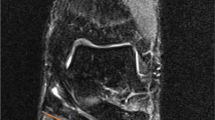

Dissection began with the removal of skin and adipose tissue of the medial ankle region, resulting in the exposure of the flexor retinaculum. After the removal of the flexor retinaculum, the structures of the tarsal tunnel were clearly visible within their own fibrous canals, separated by thick fibrous septa as supported by previous literature [18, 20]. The contents beginning most medially were the tendon of tibialis posterior, the tendon of flexor digitorum longus, the neurovascular bundle encased in neurovascular sheath, containing the PTA, PTVs and the TN, and most laterally the tendon of flexor hallucis longus (Fig. 5a, b). To accurately locate the bifurcation of the PTA, the neurovascular sheath encasing this neurovascular bundle was removed, although only where necessary to preserve the PTA’s natural position within the TT.

Exposed contents of the tarsal tunnel at the medial ankle. A Following removal of the flexor retinaculum and neurovascular sheath, the posterior tibial veins (PTVs) and posterior tibial artery (PTA) can be identified, as well as the tendon of tibialis posterior (TP) & the tendon of flexor digitorum longus (FDL). B Same specimen as 6A; however, the posterior tibial veins and posterior tibial artery have been retracted to locate the tibial nerve (TN), (compass: A Anterior, Po Posterior, Pr Proximal, D Distal)